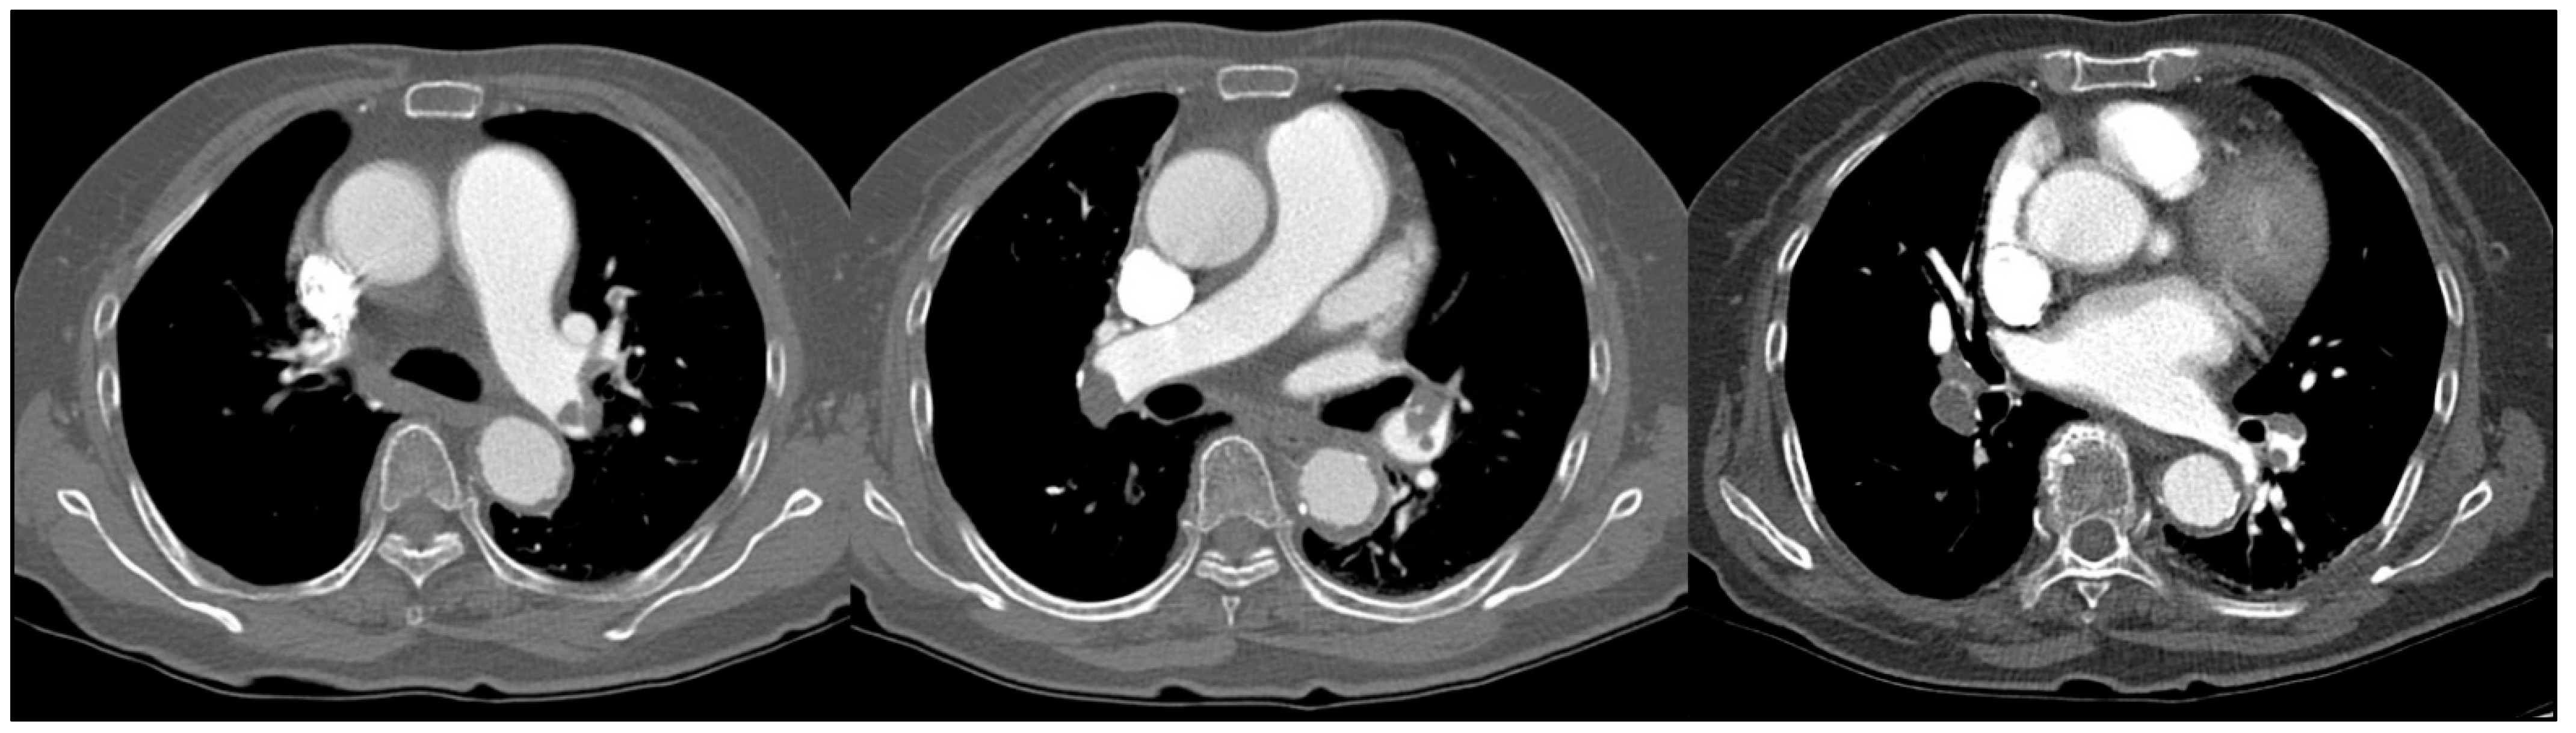

2. Case Report